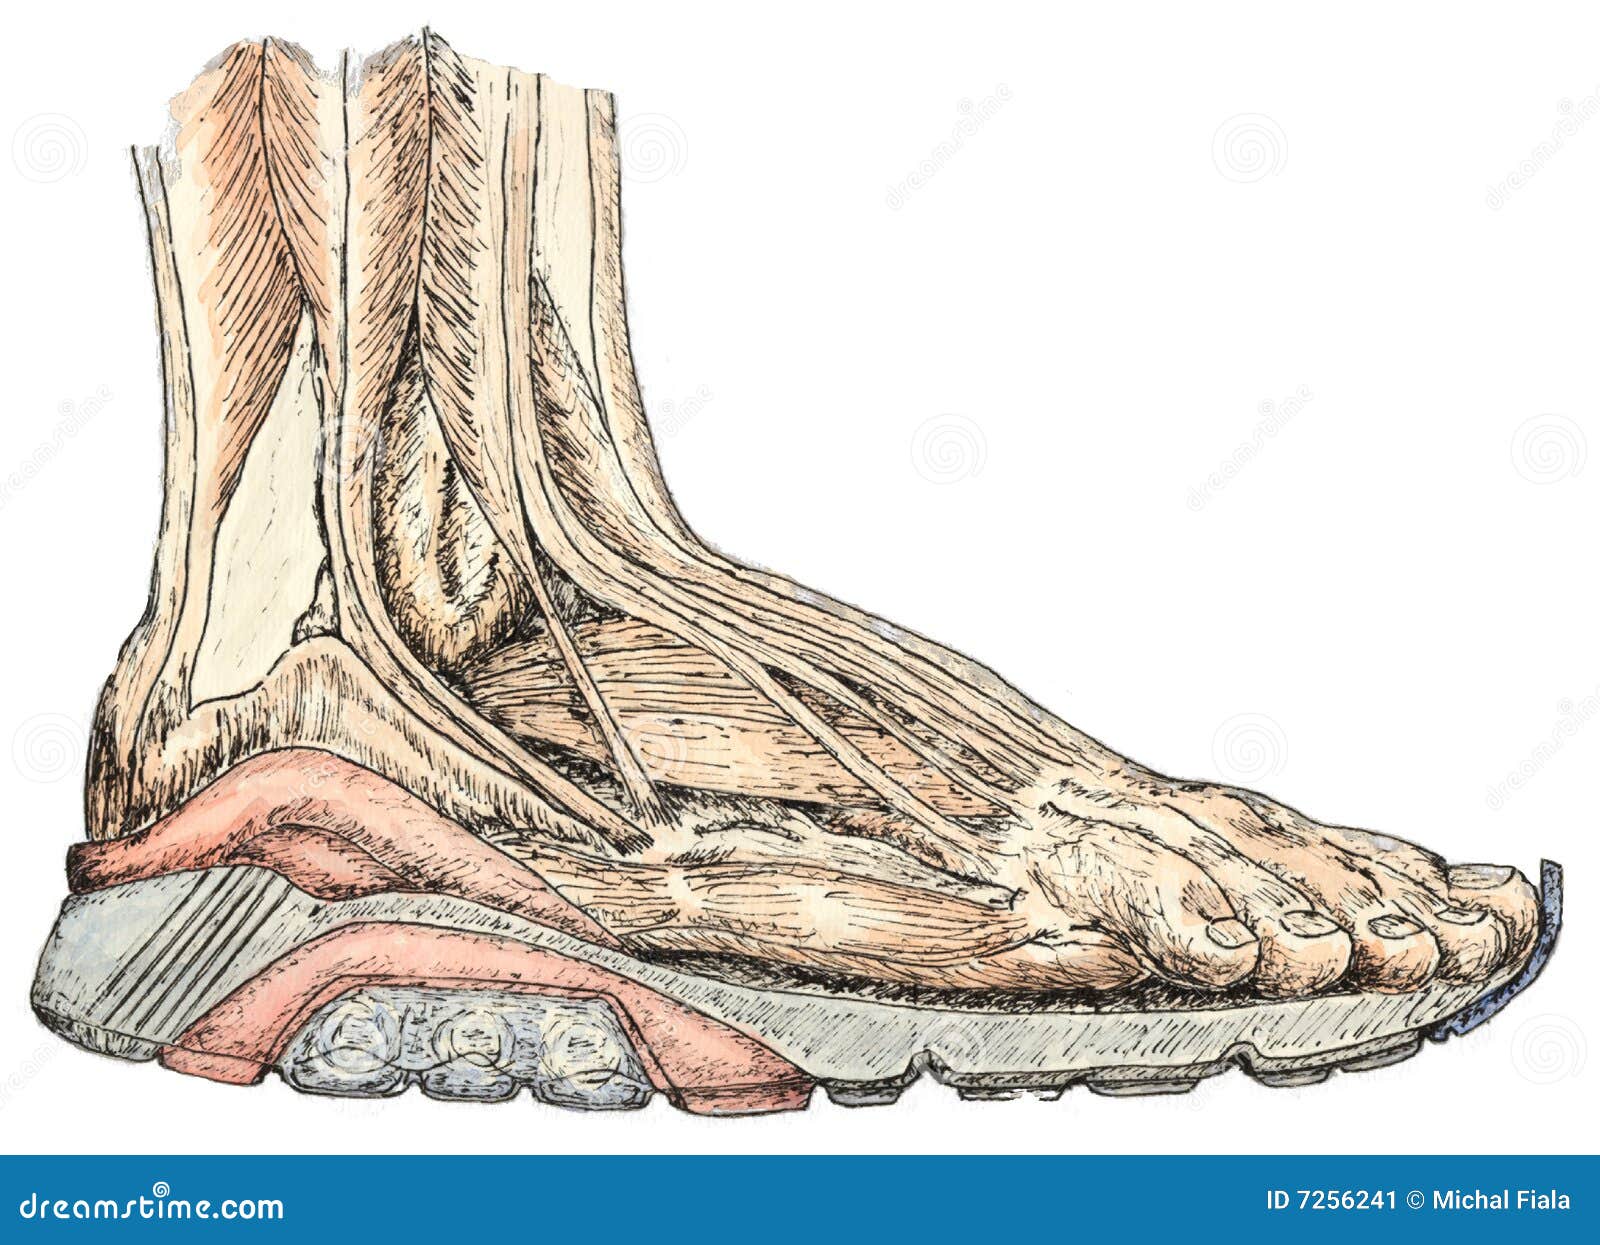

Anatomie De Pied Illustration Stock. Illustration Du Orteil - 7256241

fr.dreamstime.comvoet anatomie piede anatomia pied orteil

fr.dreamstime.comvoet anatomie piede anatomia pied orteil

it.dreamstime.comRappresentazione Dello Spaccato Di Anatomia Del Piede Umano

it.dreamstime.comRappresentazione Dello Spaccato Di Anatomia Del Piede Umano

it.dreamstime.compiede anatomia umano rappresentazione spaccato

it.dreamstime.compiede anatomia umano rappresentazione spaccato